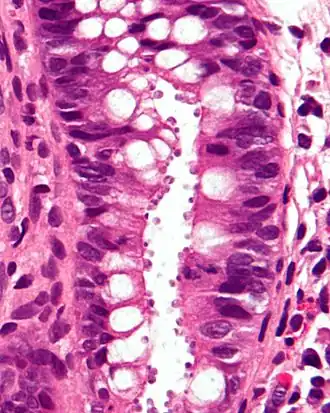

Examen au microscope optique révélant une cryptosporidiose : les cryptosporidium sont ces petits corps ronds à l'intérieur de vacuoles apicales à la surface de l'épithélium. Biopsie du côlon colorée H & E.